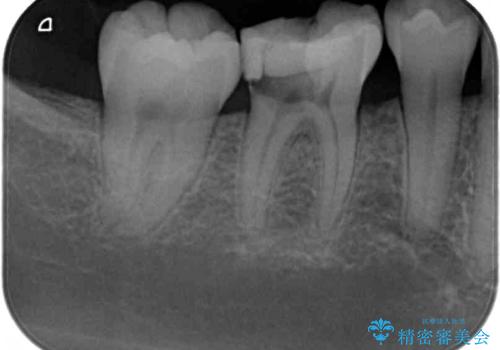

- 奥歯が食事中に歯が欠けて、しみて痛いとのことで来院された患者様です。

レントゲン写真からも、舌側に大きな虫歯があることが分かりました。

症状から神経を取り除く可能性も考慮し、オールセラミッククラウンにて補綴治療することとしました。